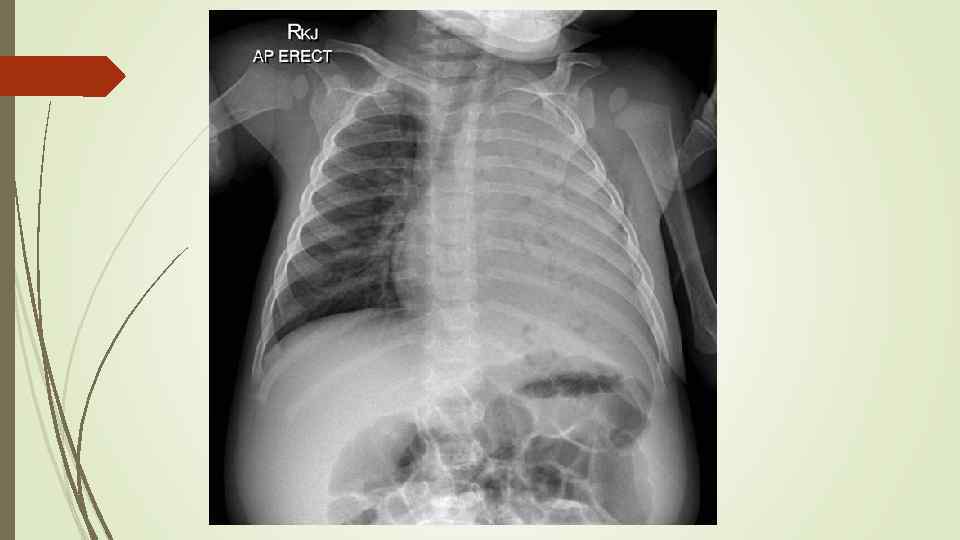

Round pneumonia

Round pneumonia